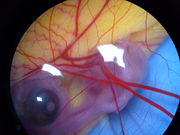

Embryo (řecky: έμβρυον, česky zárodek) je jedna z prvních fází ontogenetického (individuálního) vývoje (vývoje jedince) eukaryotického mnohobuněčného organismu, v typickém případě živočicha či rostliny.

U obratlovců jde o období od prvního rozdělení zygoty dokud se nevyvine v plod čili fétus. Embryonální období zahrnuje rýhování, vznik moruly a blastuly, diferenciaci, vývoj zárodečnýh listů a základů orgánových soustav. U člověka se jedná od období od 2. do 8. (nebo 10.) týdne intrauterinního vývoje, kdy se tvoří ze dvou zárodečných listů zárodečný terčík a tvoří se hlavní orgánové základy. Embryonální vývoj je tak vlastně pouze jedním ze tří stadií, jimiž vyvíjející se jedinec prochází: